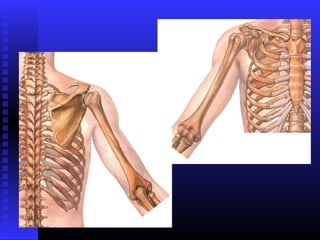

OSSOS DO MEMBRO SUPERIOROSSOS DO MEMBRO SUPERIOR